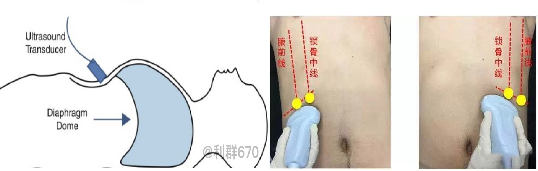

膈肌活动度检查

探头:低频探头

部位:放置在腋前线或锁骨中线与肋缘交界处,启用M模式取样线垂直于膈肌,观察和测量膈肌运动幅度。

功能:M超,膈肌测量包

膈肌活动度测量